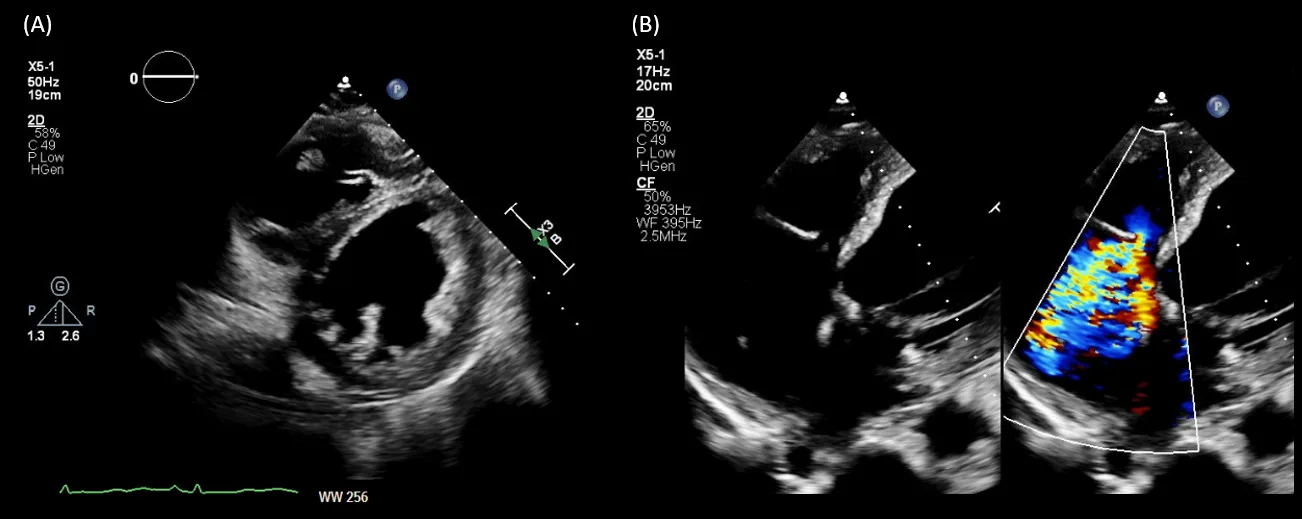

Interestingly, the patient lacked pedal edema or shortness of breath. A formal echocardiogram demonstrated reduction of left ventricular ejection fraction from a baseline of 37% to ~30%, new right ventricular enlargement with interventricular septal flattening (D-sign), and severe functional tricuspid regurgitation, suggestive of fluid overload (Figure 3). The patient history was not suggestive of pulmonary embolism. A nuclear medicine stress test was negative for ischemic changes. Over the subsequent three days, the nephrology team performed daily ultrafiltration, resulting in removal of 8 liters of fluid (net negative 4.5 liters on day 3). At the end of the second session, the nephrology team performed a follow up VExUS scan that showed significant improvement in the congestion. The portal vein was completely normalized, whereas the hepatic vein showed mild congestion with S-wave less than D-wave. A simultaneous ECG tracing was used to avoid errors in misidentification of the waves (Figure 4).

Figure 3. Formal echocardiogram images demonstrating (A) interventricular septal flattening on parasternal short axis view and (B) qualitatively severe tricuspid regurgitation.